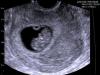

Наша первая фотография! муж очень рад! и ему все ровно кто там будет! главное что бы здоровенький (ая) ! А я бы очень хотела мальчика!

@katrinkatrin2001, у автора даже в УЗИ видно, что написано в полости матки одно плодное яйцо)

@katrinkatrin2001, я не пугаю. То чёрное продолговатое сплющенное - это яйцо, внутри эмбриончик. Сплющило его скорей всего от тонуса.

По снимку похоже у вас сильный тонус, яйцо сплющило. Вы ко врачу с этим УЗИ ходили уже?